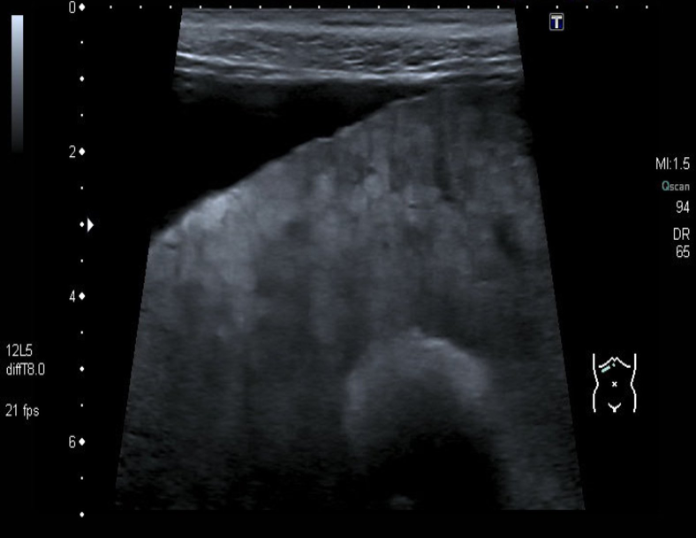

Decompensated liver cirrhosis

- Ultrasound liver (oblique view)

- Heterogeneous liver parenchyma, nodular liver margin, and ascites can be seen.

- These findings are consistent with decompensated liver cirrhosis.